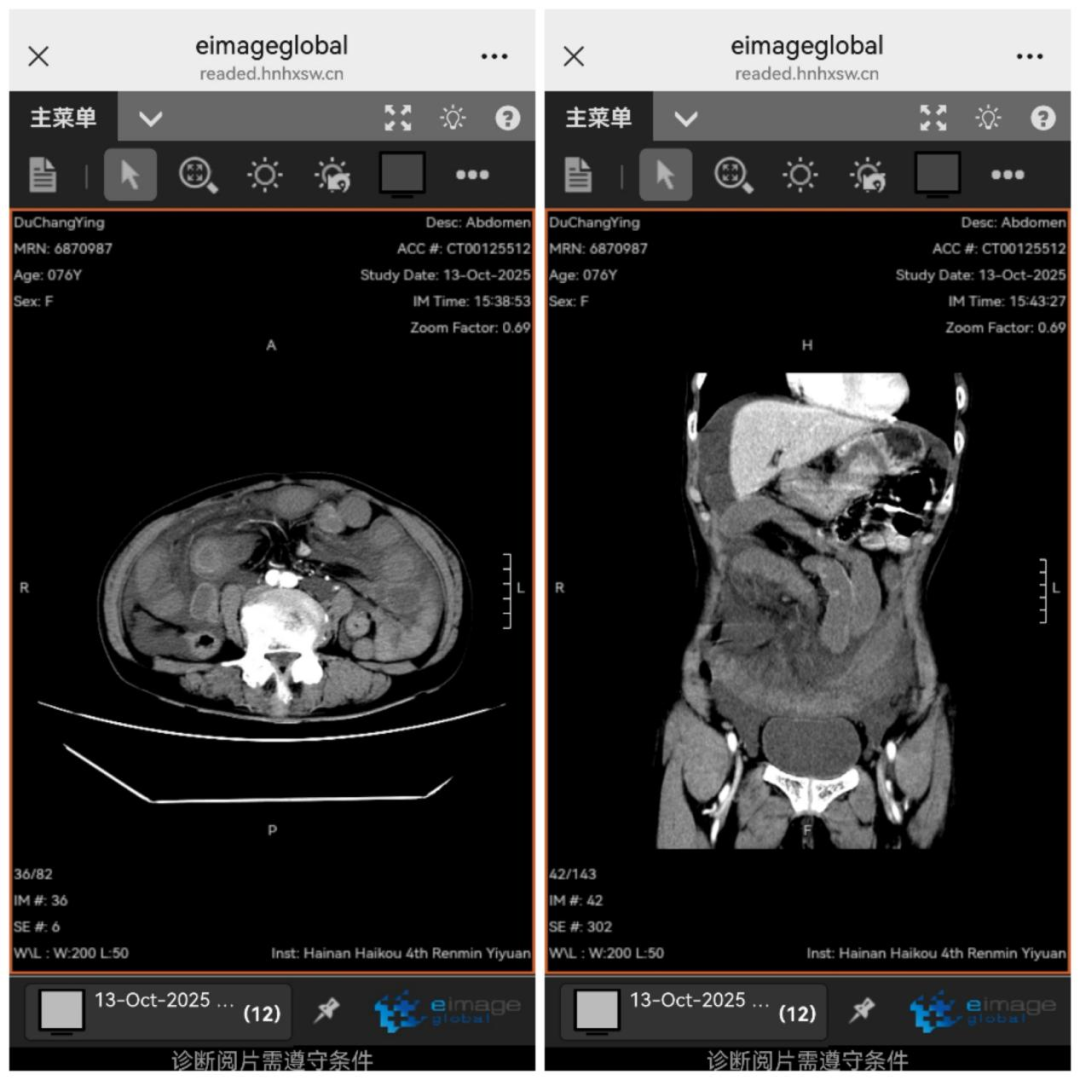

入科后,普通外科刘琪主任仔细检查,发现患者突发剧烈腹痛、腹肌软、中下腹部压痛、无明显腹胀,起病时间短,无典型肠梗阻症状。与放射科共同阅片后,考虑小肠肠管水肿,刘琪主任判断闭袢性小肠梗阻可能性极大,同时稳定患者生命体征,立即安排腹部增强CT检查。

检查显示,患者腹部积液快速增多,肠管扩张增厚。刘琪主任指出病情急剧恶化,疼痛可能引发疼痛性休克,体液快速丢失会导致失血性休克,肠道坏死细菌外移,坏死组织释放的炎性介质会冲击多脏器功能。时间紧迫,必须立即手术探查。随后,麻醉科蔡弥松主任、重症医学科吴清松主任应邀协诊,共同制定围手术期治疗方案。在患者家属充分信任下,手术迅速展开。

术中发现,腹腔内有约1000ml血性积液,大网膜与回肠系膜形成长约1.5米的粘连带,小肠扭转坏死。